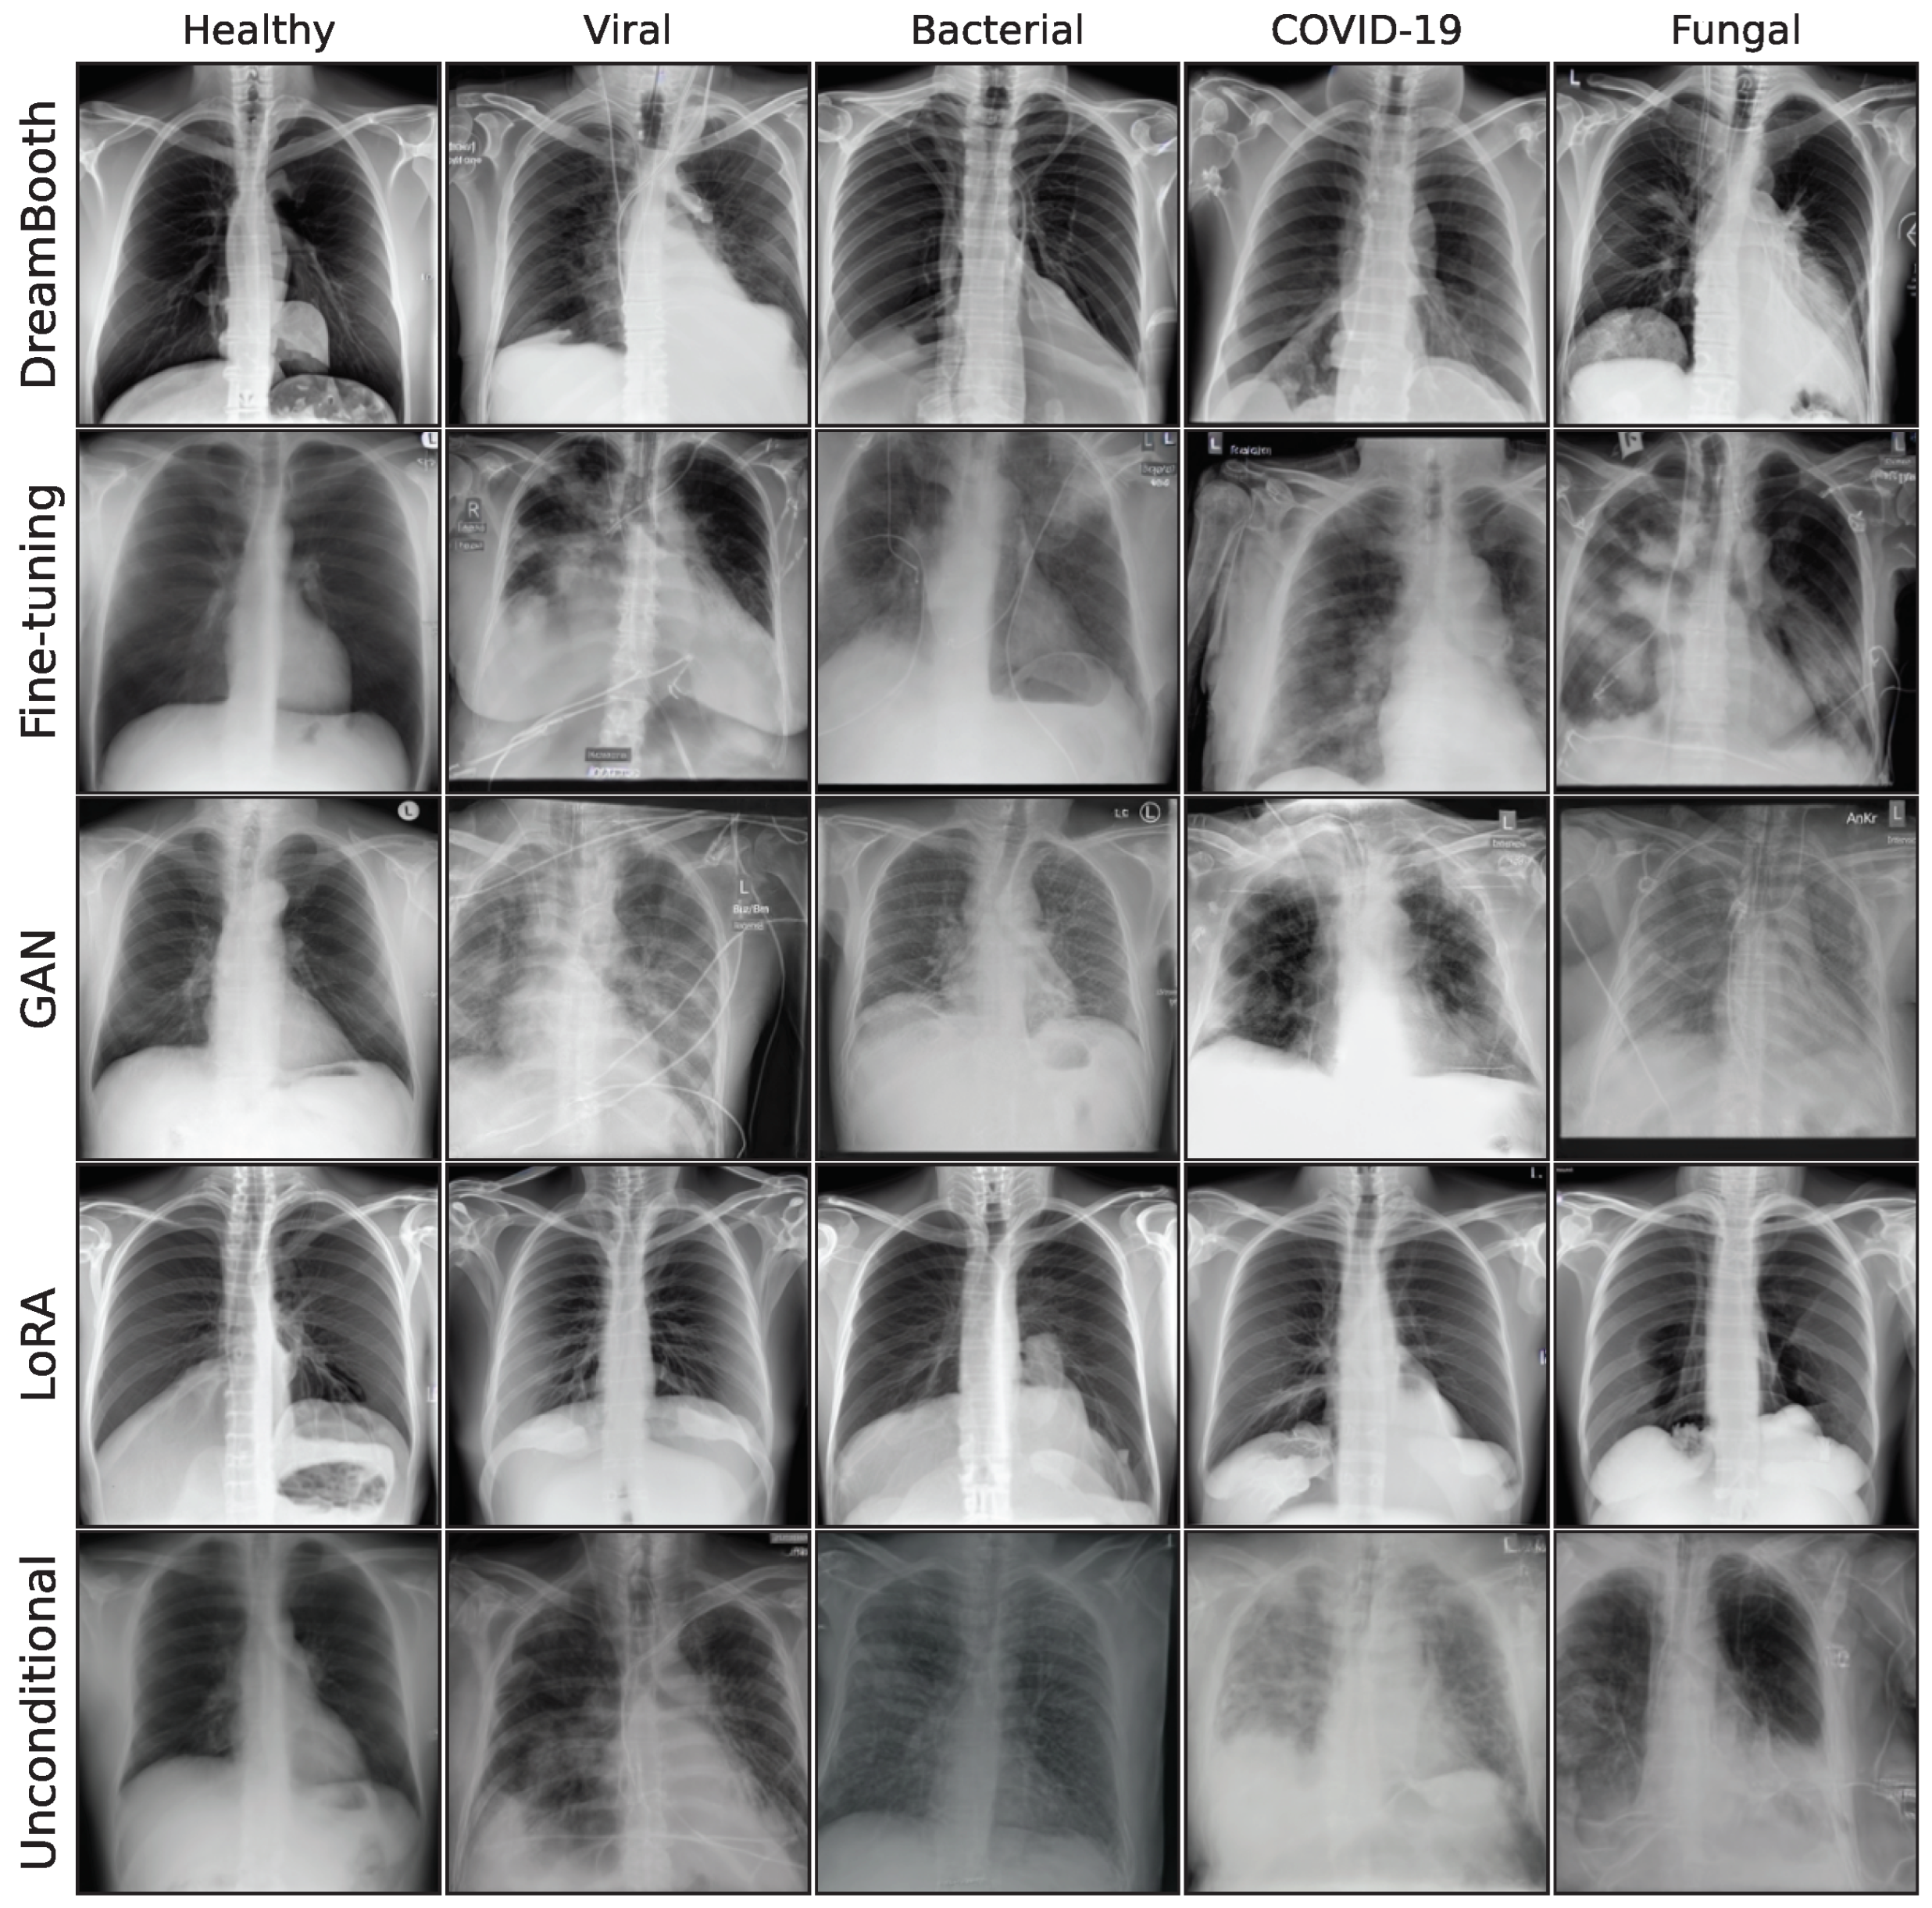

3.2. Image Synthesis

Figure A2. Sample synthetic images from all classes and methods.